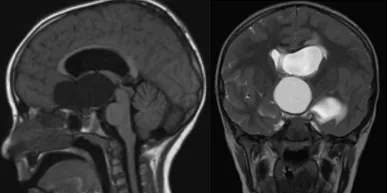

9岁女性患者拉拉平日喜爱自然活动,经常与家人进行户外游玩。某次行程结束后,患者在乘车过程中突发头痛症状。初期被认为是活动劳累所致,但随后数日头痛症状持续存在。就诊时患儿出现视力障碍表现,进一步检查确诊为巨大颅咽管瘤。肿瘤形态类似球形结构,对患者家庭造成重大心理冲击。